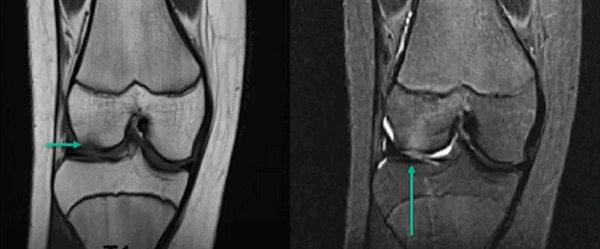

МР-скан коленного сустава в Т1 режиме (стрелкой указан костный отек)

МР-снимок коленного сустава в режиме Т2, контузия кости

МР-изображение субхондрального перелома латерального мыщелка (зона повреждения указана стрелкой)